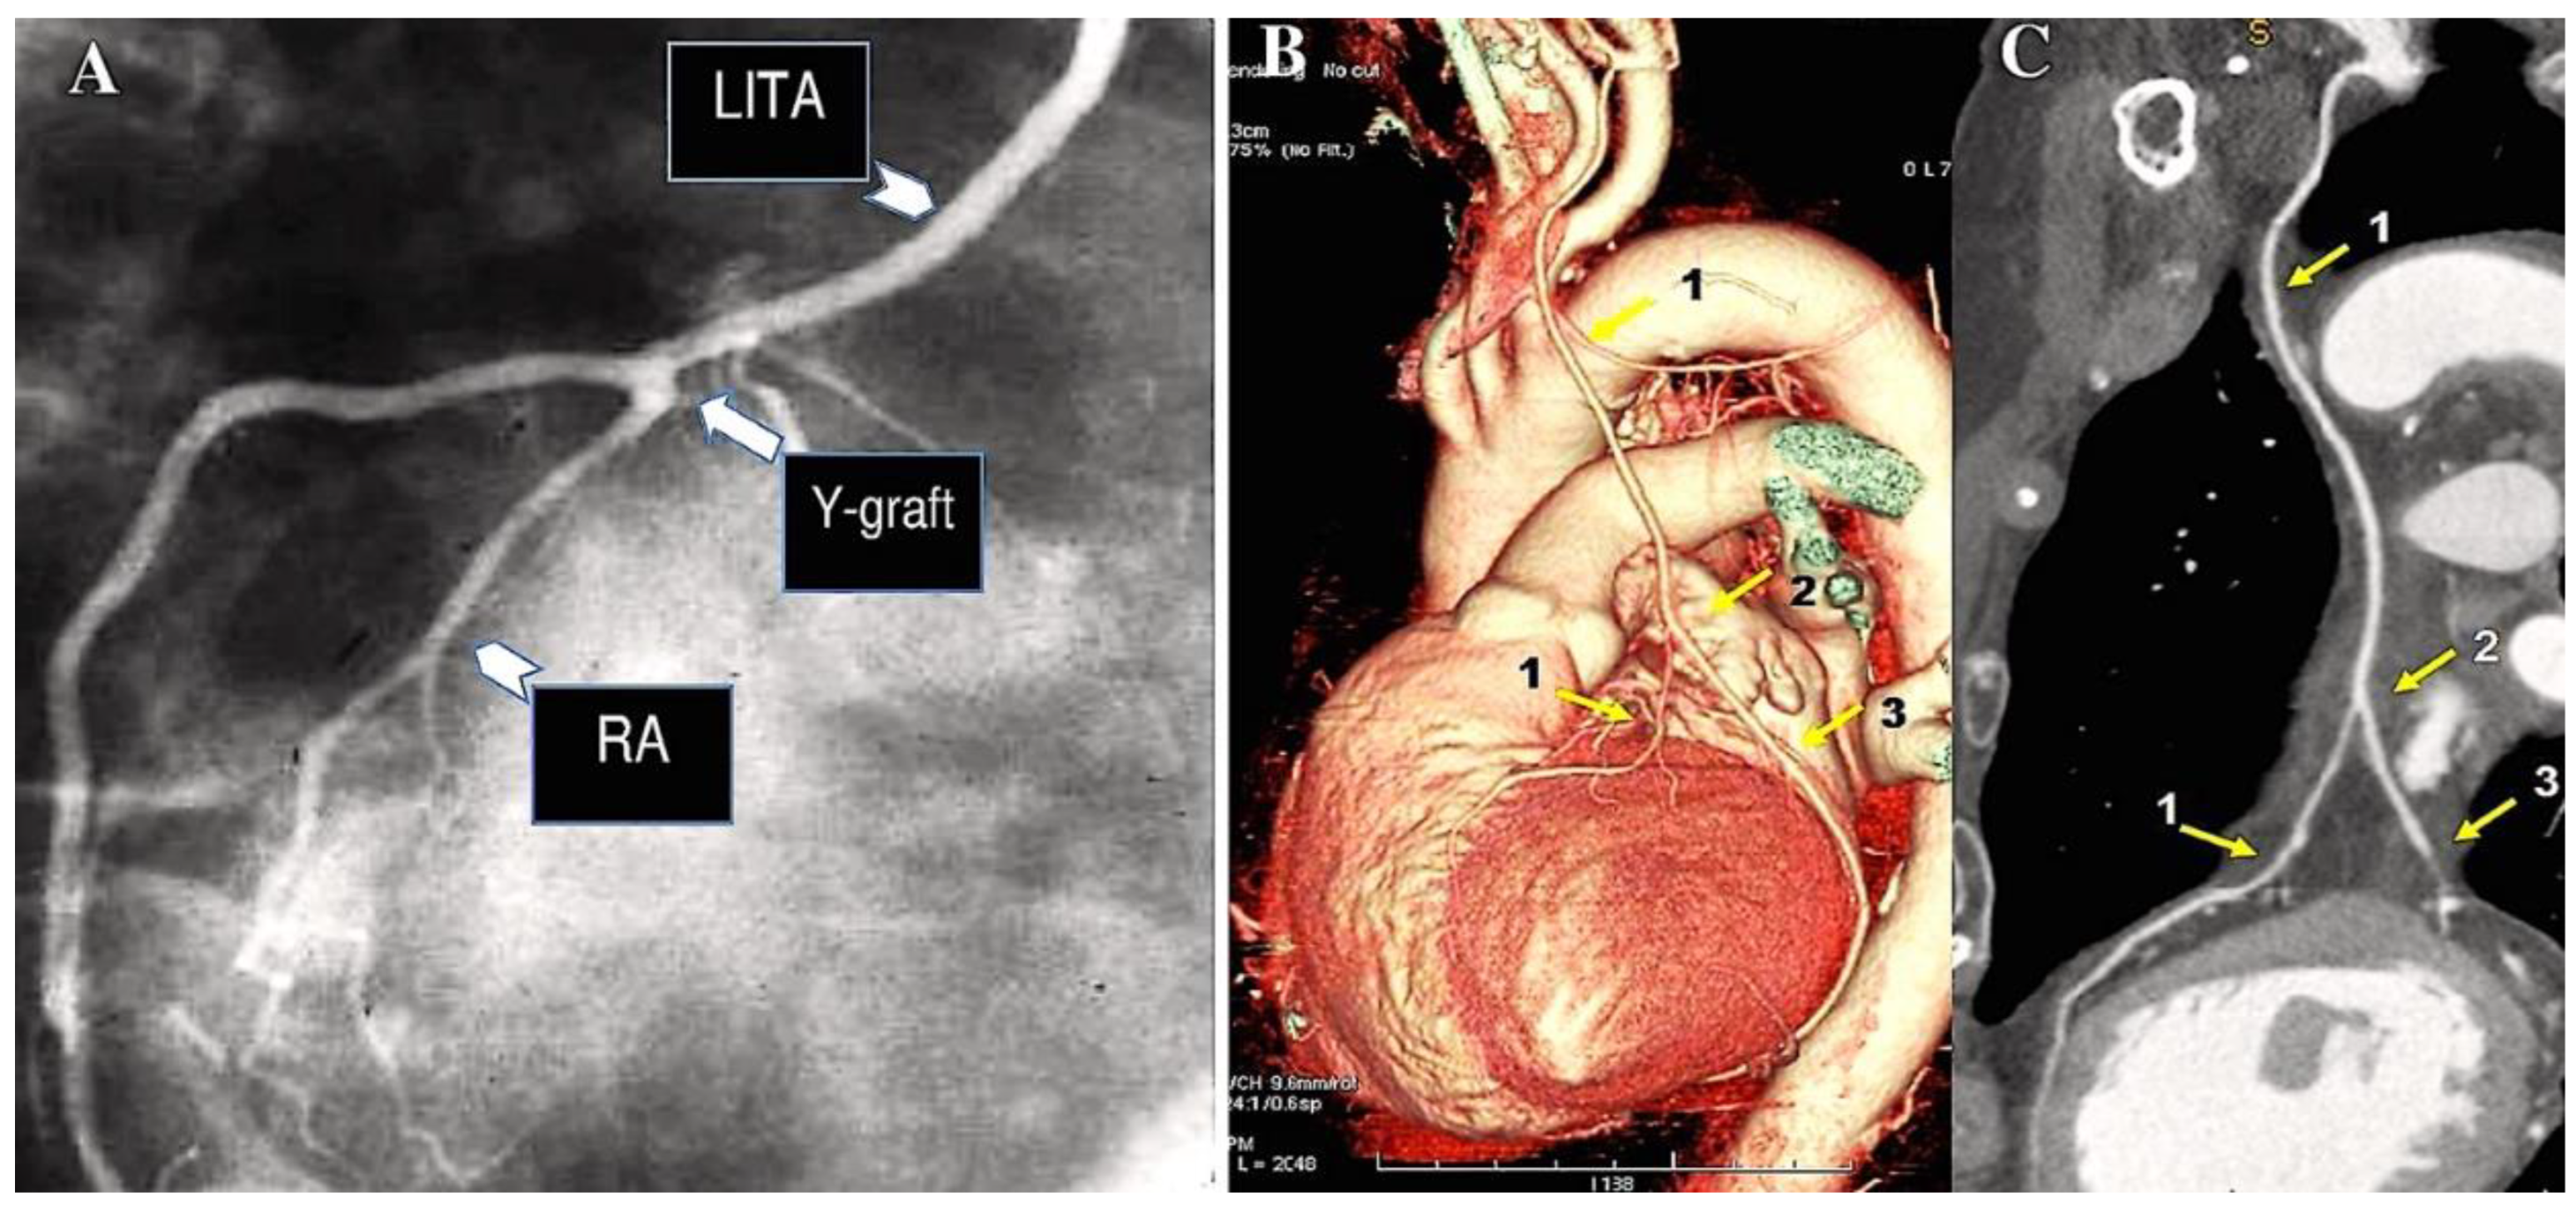

- Royse AG, Brennan AP, Ou-Young J, Pawanis Z, Canty DJ, Royse CF. 21 Year Survival of Left Internal Mammary Artery-Radial Artery-Y Graft. J Am Coll Cardiol. 2018 Sep 18;72(12):1332-1340. [CrossRef]

- Calafiore AM, Di Giammarco G, Luciani N, Maddestra N, Di Nardo E, Angelini R. Composite arterial conduits for a wider arterial myocardial revascularization. Ann Thorac Surg. 1994 Jul;58(1):185-90 . [CrossRef]

- Nasso G, Coppola R, Bonifazi R, Piancone F, Bozzetti G, Speziale G. Arterial revascularization in primary coronary artery bypass grafting: Direct comparison of 4 strategies-results of the Stand-in-Y Mammary Study. J Thorac Cardiovasc Surg 2009. 137:1093-100. [CrossRef]

- Lemma M, Mangini A, Gelpi G, Innorta A, Spina A, Antona C. Is it better to use the radial artery as a composite graft? Clinical and angiographic results of aorto-coronary versus Y-graft. Eur J Cardiothorac Surg 2004. 26:110–117. [CrossRef]

- Jung SH, Song H, Choo SJ, Je HG, Chung CH, Kang JW, Lee JW. Comparison of radial artery patency according to proximal anastomosis site: direct aorta to radial artery anastomosis is superior to radial artery composite grafting. J Thorac Cardiovasc Surg 2009. 138:76-83. [CrossRef]